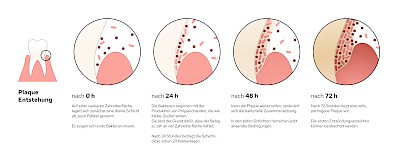

Plaque (Biofilm)

Als Plaque bzw. Biofilm bezeichnet man die Gesamtheit aller Mikroorganismen (Mikrobiom) auf der Zahnoberfläche. Werden die Zähne nicht geputzt, haften die Beläge nach 24 Stunden bereits so fest, dass diese mit der Zahnbürste schon nicht mehr vollständig entfernt werden können.

Im Anfangsstadium kann Plaque (Biofilm) durch Optimierung und Intensivierung der Mundhygiene (Zähneputzen mit Zahnpasta) noch reduziert werden. Lassen sich die Beläge mit Zahnbürste und Zahnpasta nicht mehr entfernen, muss der Zahnarzt unterstützen.